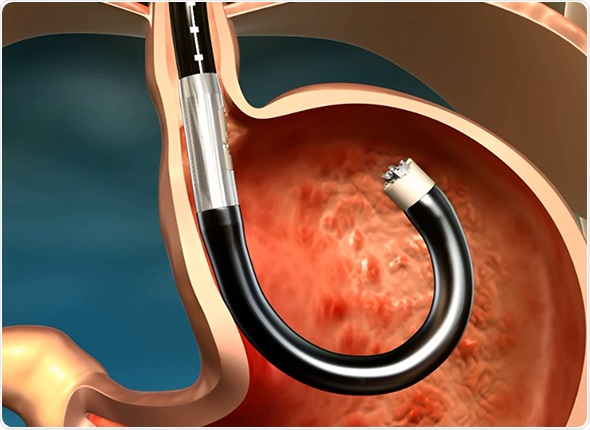

The MUSE system is an intuitive, endoscopic platform for the long-term, possibly permanent, treatment of GERD. It is equipped with the latest technological advancements in microvisualization, ultrasound and surgical stapling, thereby allowing a single physician or surgeon to perform anterior partial fundoplication more easily than with leading laparoscopic methods.

Its platform consists of a single use flexible surgical endostapler, equipped with a proprietary miniature camera, an ultrasonic sight and a range finder, and includes a handle with controls, an 80cm flexible shaft, a 5cm rigid section holding a cartridge with 5 standard 4.8mm titanium surgical staples, a ratchet controlled one-way articulating section, and a distal tip.

The MUSE endostapler is progressed into the stomach through an overtube and retroflexed under direct video guidance. After identifying an ideal stapling location, the stapler is gently pulled back to place the staple cartridge in the lower esophagus approximately 3cm above the gastroesophageal junction. The procedure typically delivers about five staples to effectively reinforce the LES.